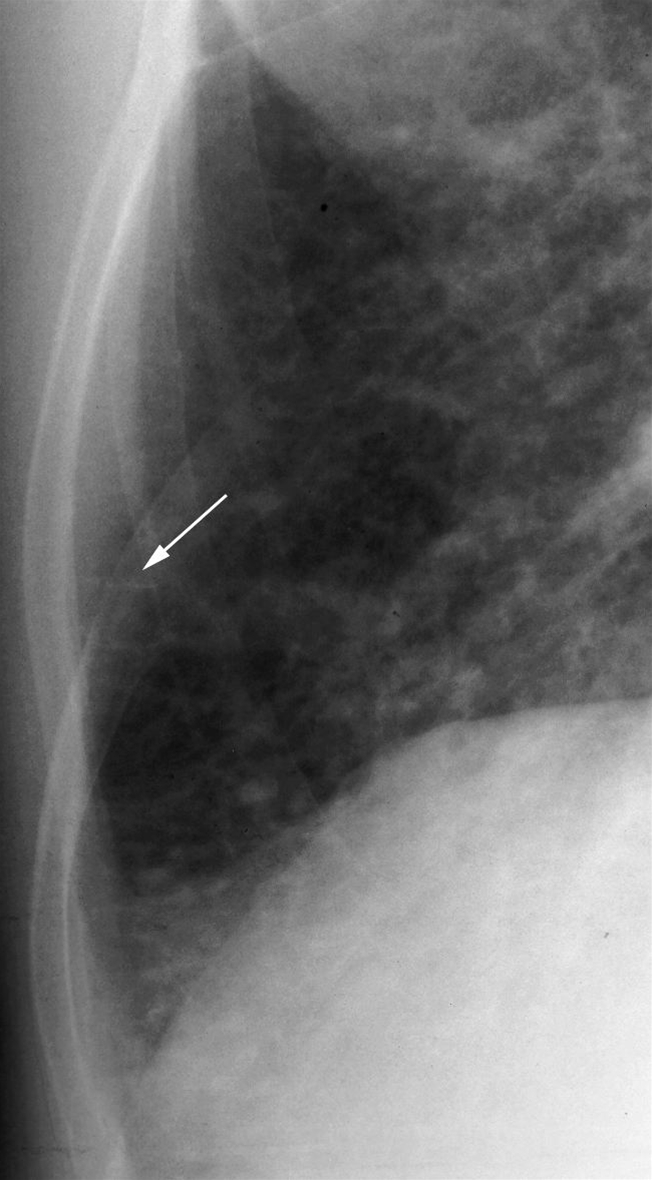

Hjertesvigt, røntgen, Kerley B line

"Kerley B linjer" (pil) som er fortykkede interlobulærsepta på grund af øget væskemængde.